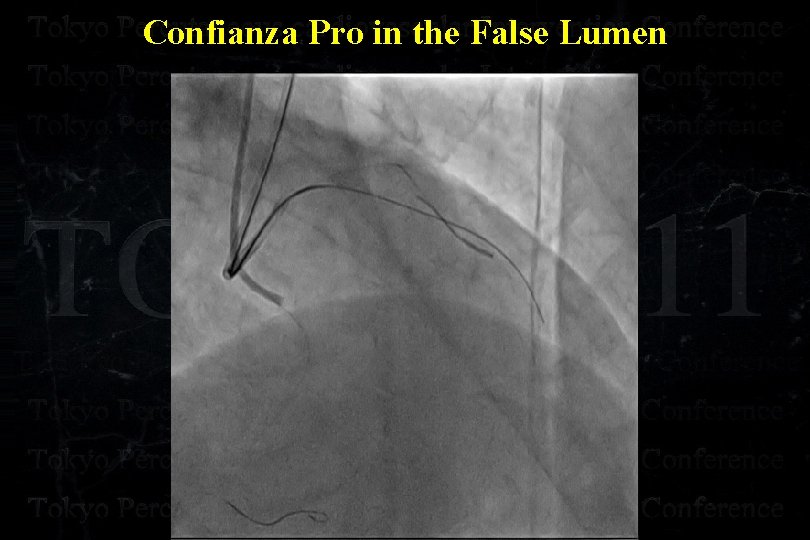

Confianza Pro in the False Lumen